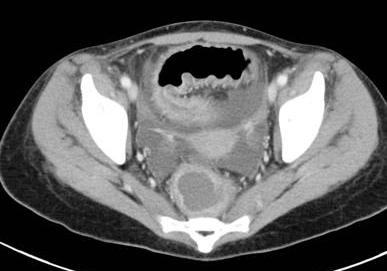

. Image TDM du maladie de

Crohn dans phase aigue est image

de epaissisement parietale avec oedeme sous muqueuse

discontinunite et signe de peigne " comb sign ". En phase

chronique cicatricielle ,aspect radiologique est image

epaissisement homogene de la paroi avec infiltration graisseuse parietale ou mesenterique

en forme de image de cible " fat halo sign". Stenose ,fistule et

abces sont des images de sa complication .

Stenose epaisissement colique

gauche et sigmoidienne avec halo graisseux d'une

maladie de Crohn . Image de hypervascularisation et

infiltration de la graisse sous-muqueuse , aspect en

peigne " Comb sign ". Image TDM en coupe coronale |

Image de

hypervascularisation " Comb sign " et epaissisement

de la paroi du ileon se voyait si nette sur les

coupe TDM axiale |